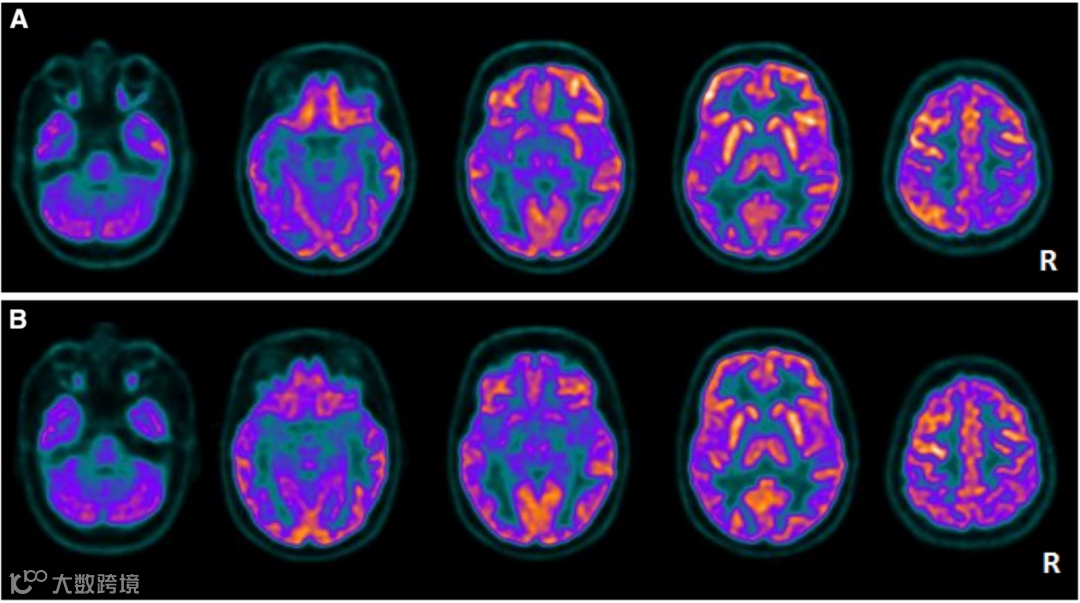

激素治疗前后两次FDG PET扫描,间隔6个月。基线扫描显示双侧纹状体、双侧颞叶、双侧枕叶糖代谢减低侧别性不著。

a 左侧颞叶、脑岛、同侧枕颞交界区及右侧顶上小叶深度低代谢

b 经血浆置换治疗三个月后脑葡萄糖代谢恢复正常。

桥本脑病的FDG PET可以提示炎症受累区域,通常呈现糖代谢减低,可为单侧,亦可为双侧多发;皮层与核团均可累及,与临床症状相关。FDG PET也可以作为桥本脑病的治疗后评估的影像学手段,在一些解剖结构受损不可逆的病人中可以通过SUV的变化来评价治疗效果。